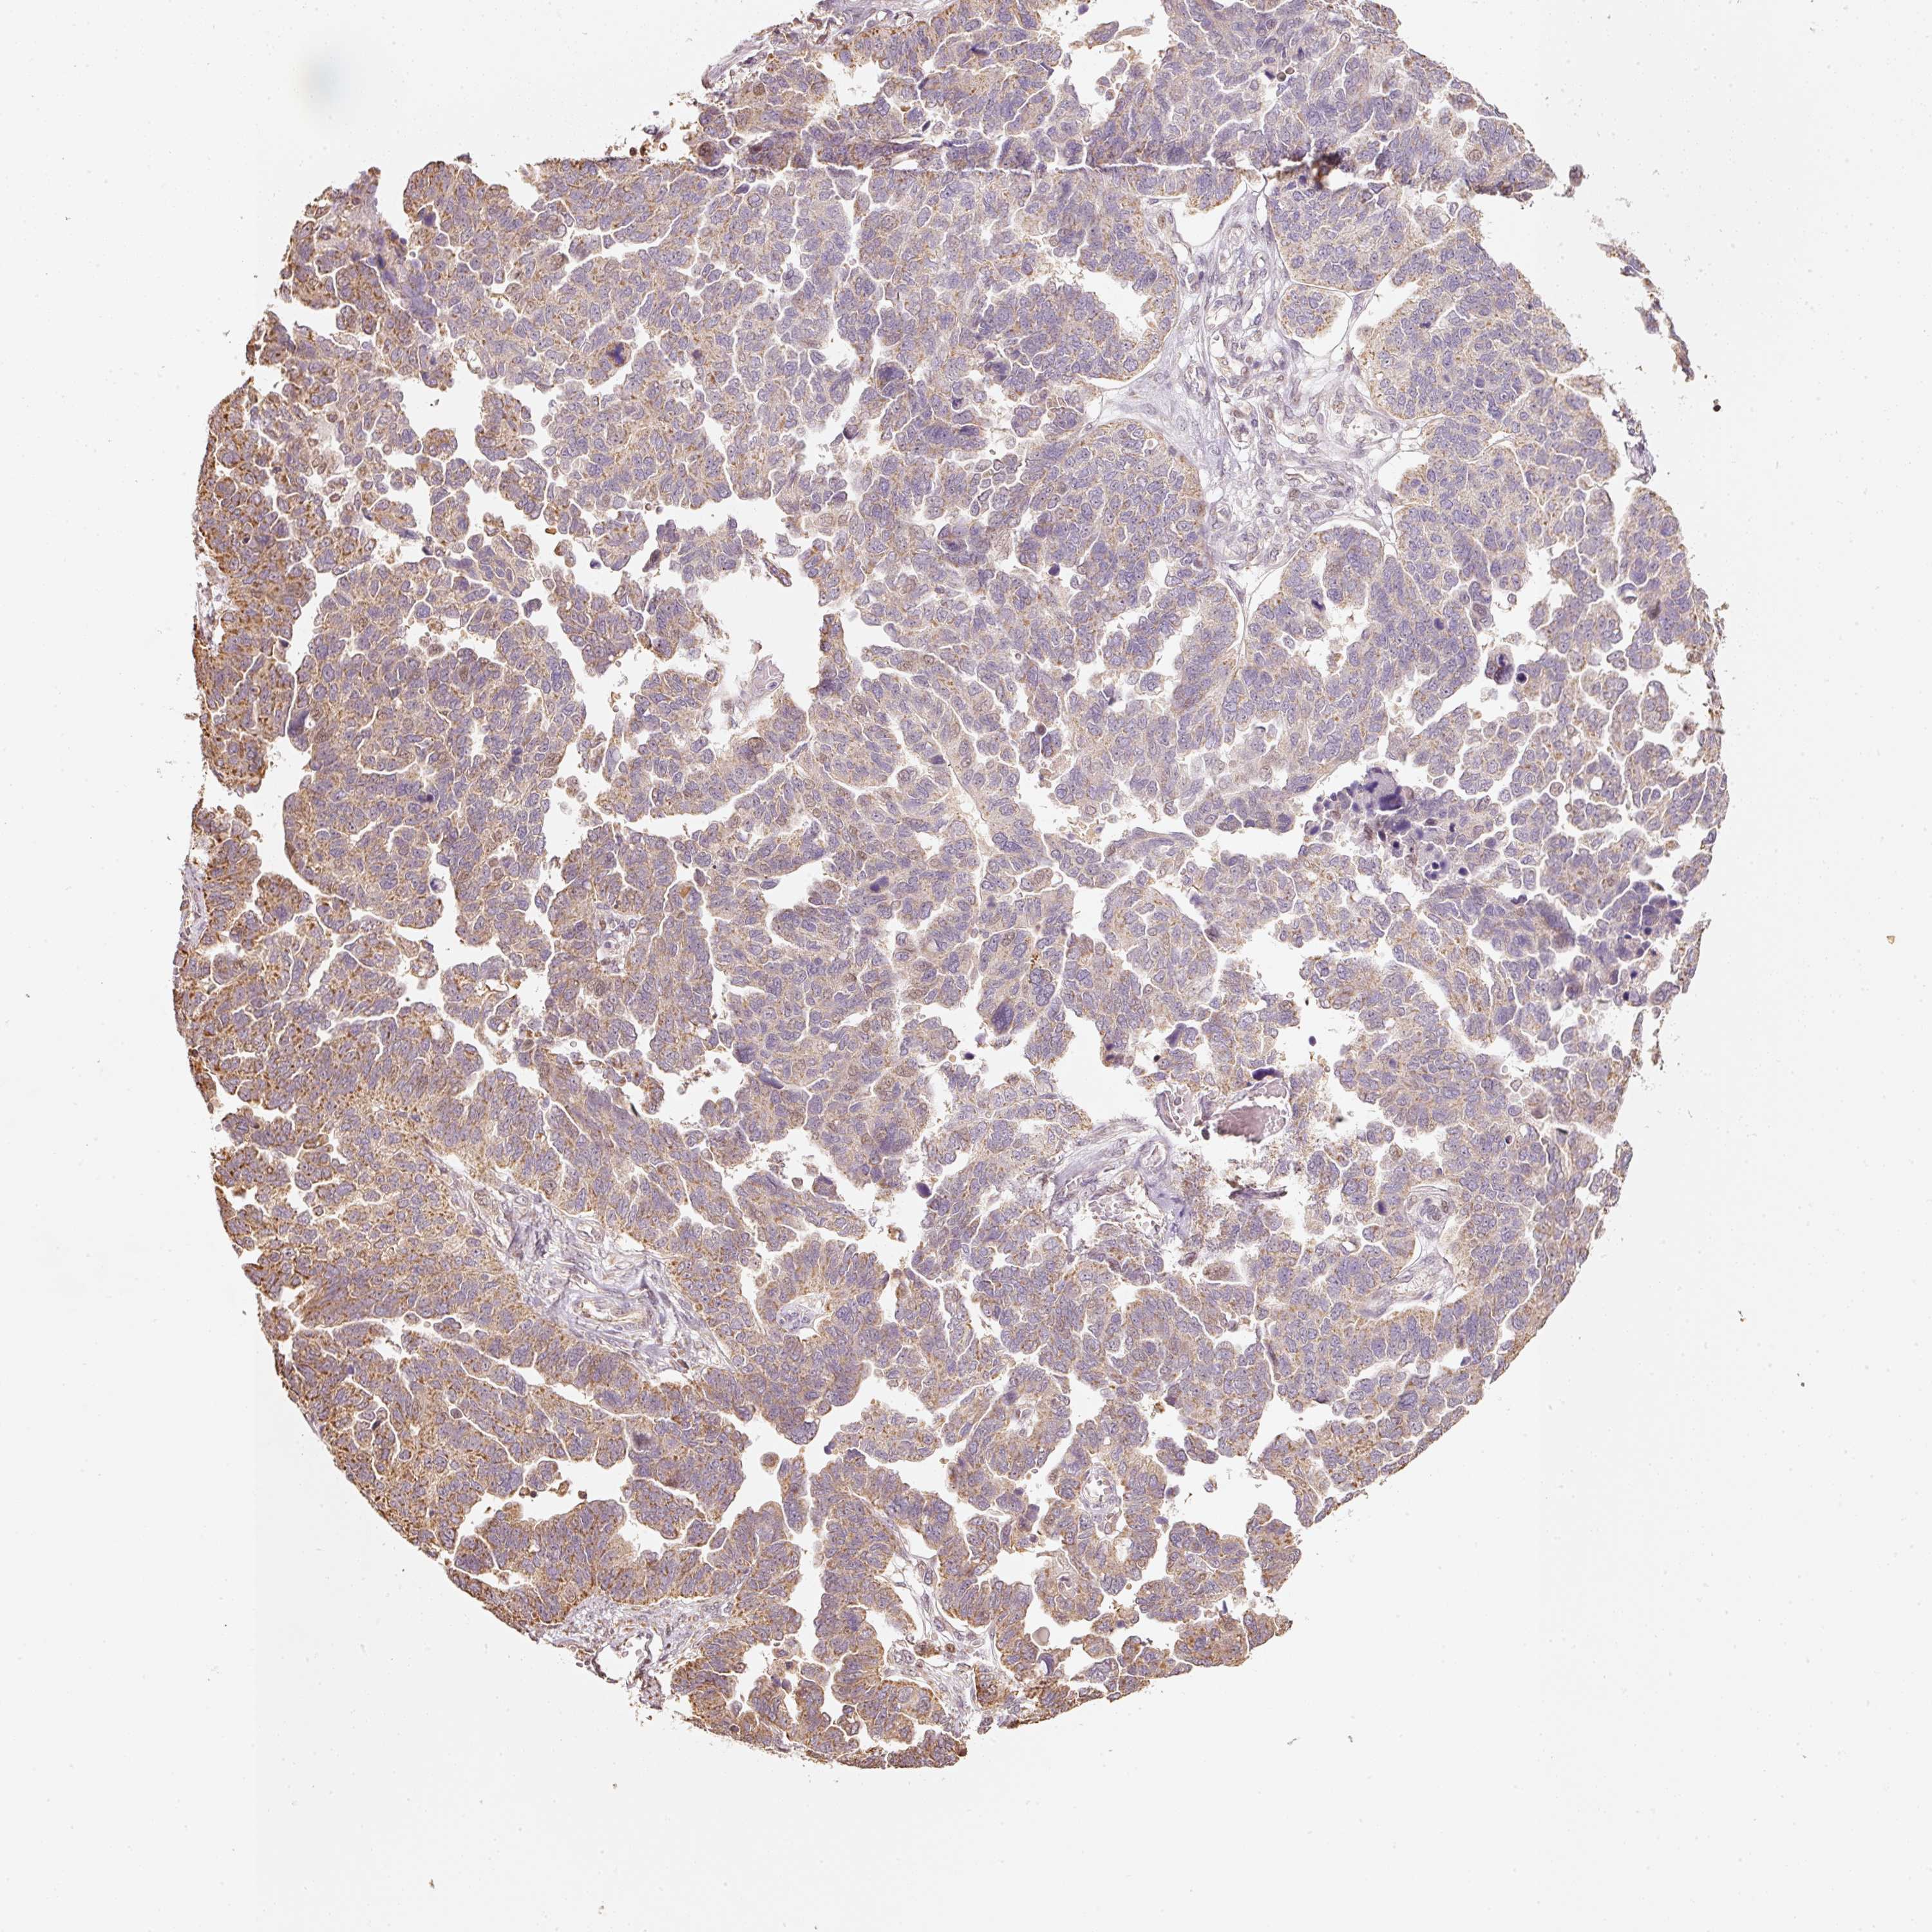

OVARIAN CANCER - Protein expressioni

A mouse-over function shows sample information and annotation data. Click on an image to view it in a full screen mode. Samples can be filtered based on level of antibody staining by selecting one or several of the following categories: high, medium, low and not detected. The assay and annotation is described here.

Note that samples used for immunohistochemistry by the Human Protein Atlas do not correspond to samples in the TCGA dataset.

Antibody stainingi

Antibody staining in the annotated cell types in the current human tissue is reported as not detected, low, medium, or high, based on conventional immunohistochemistry profiling in selected tissues. This score is based on the combination of the staining intensity and fraction of stained cells.

Each image is clickable and will lead to virtual microscopy that enables deeper exploration of all samples and also displays staining intensity scores, fraction scores and subcellular localization as well as patient and tissue information for each sample.

Antibody HPA054146

Staining

High

Medium

Low

Not detected

Intensity

Strong

Moderate

Weak

Negative

Quantity

>75%

75%-25%

<25%

None

Location

Nuclear

Cytoplasmic/membranous

Cytoplasmic/membranous,nuclear

Cystadenocarcinoma, serous, NOS